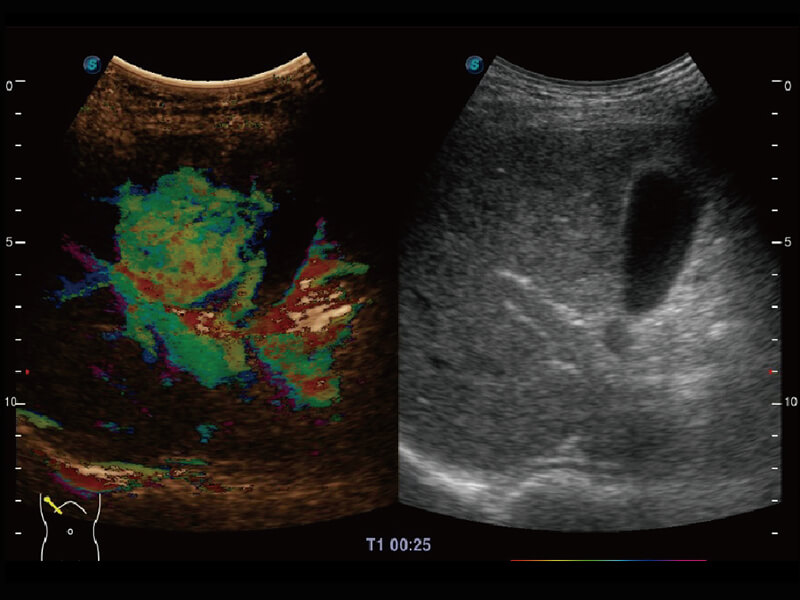

性能优异的硬件架构,极大提升超声系统的运行效率和数据处理能力。相比以往超声成像系统,Wis+平台为您带来极快的响应速度和成像帧频,提升检查流畅度。